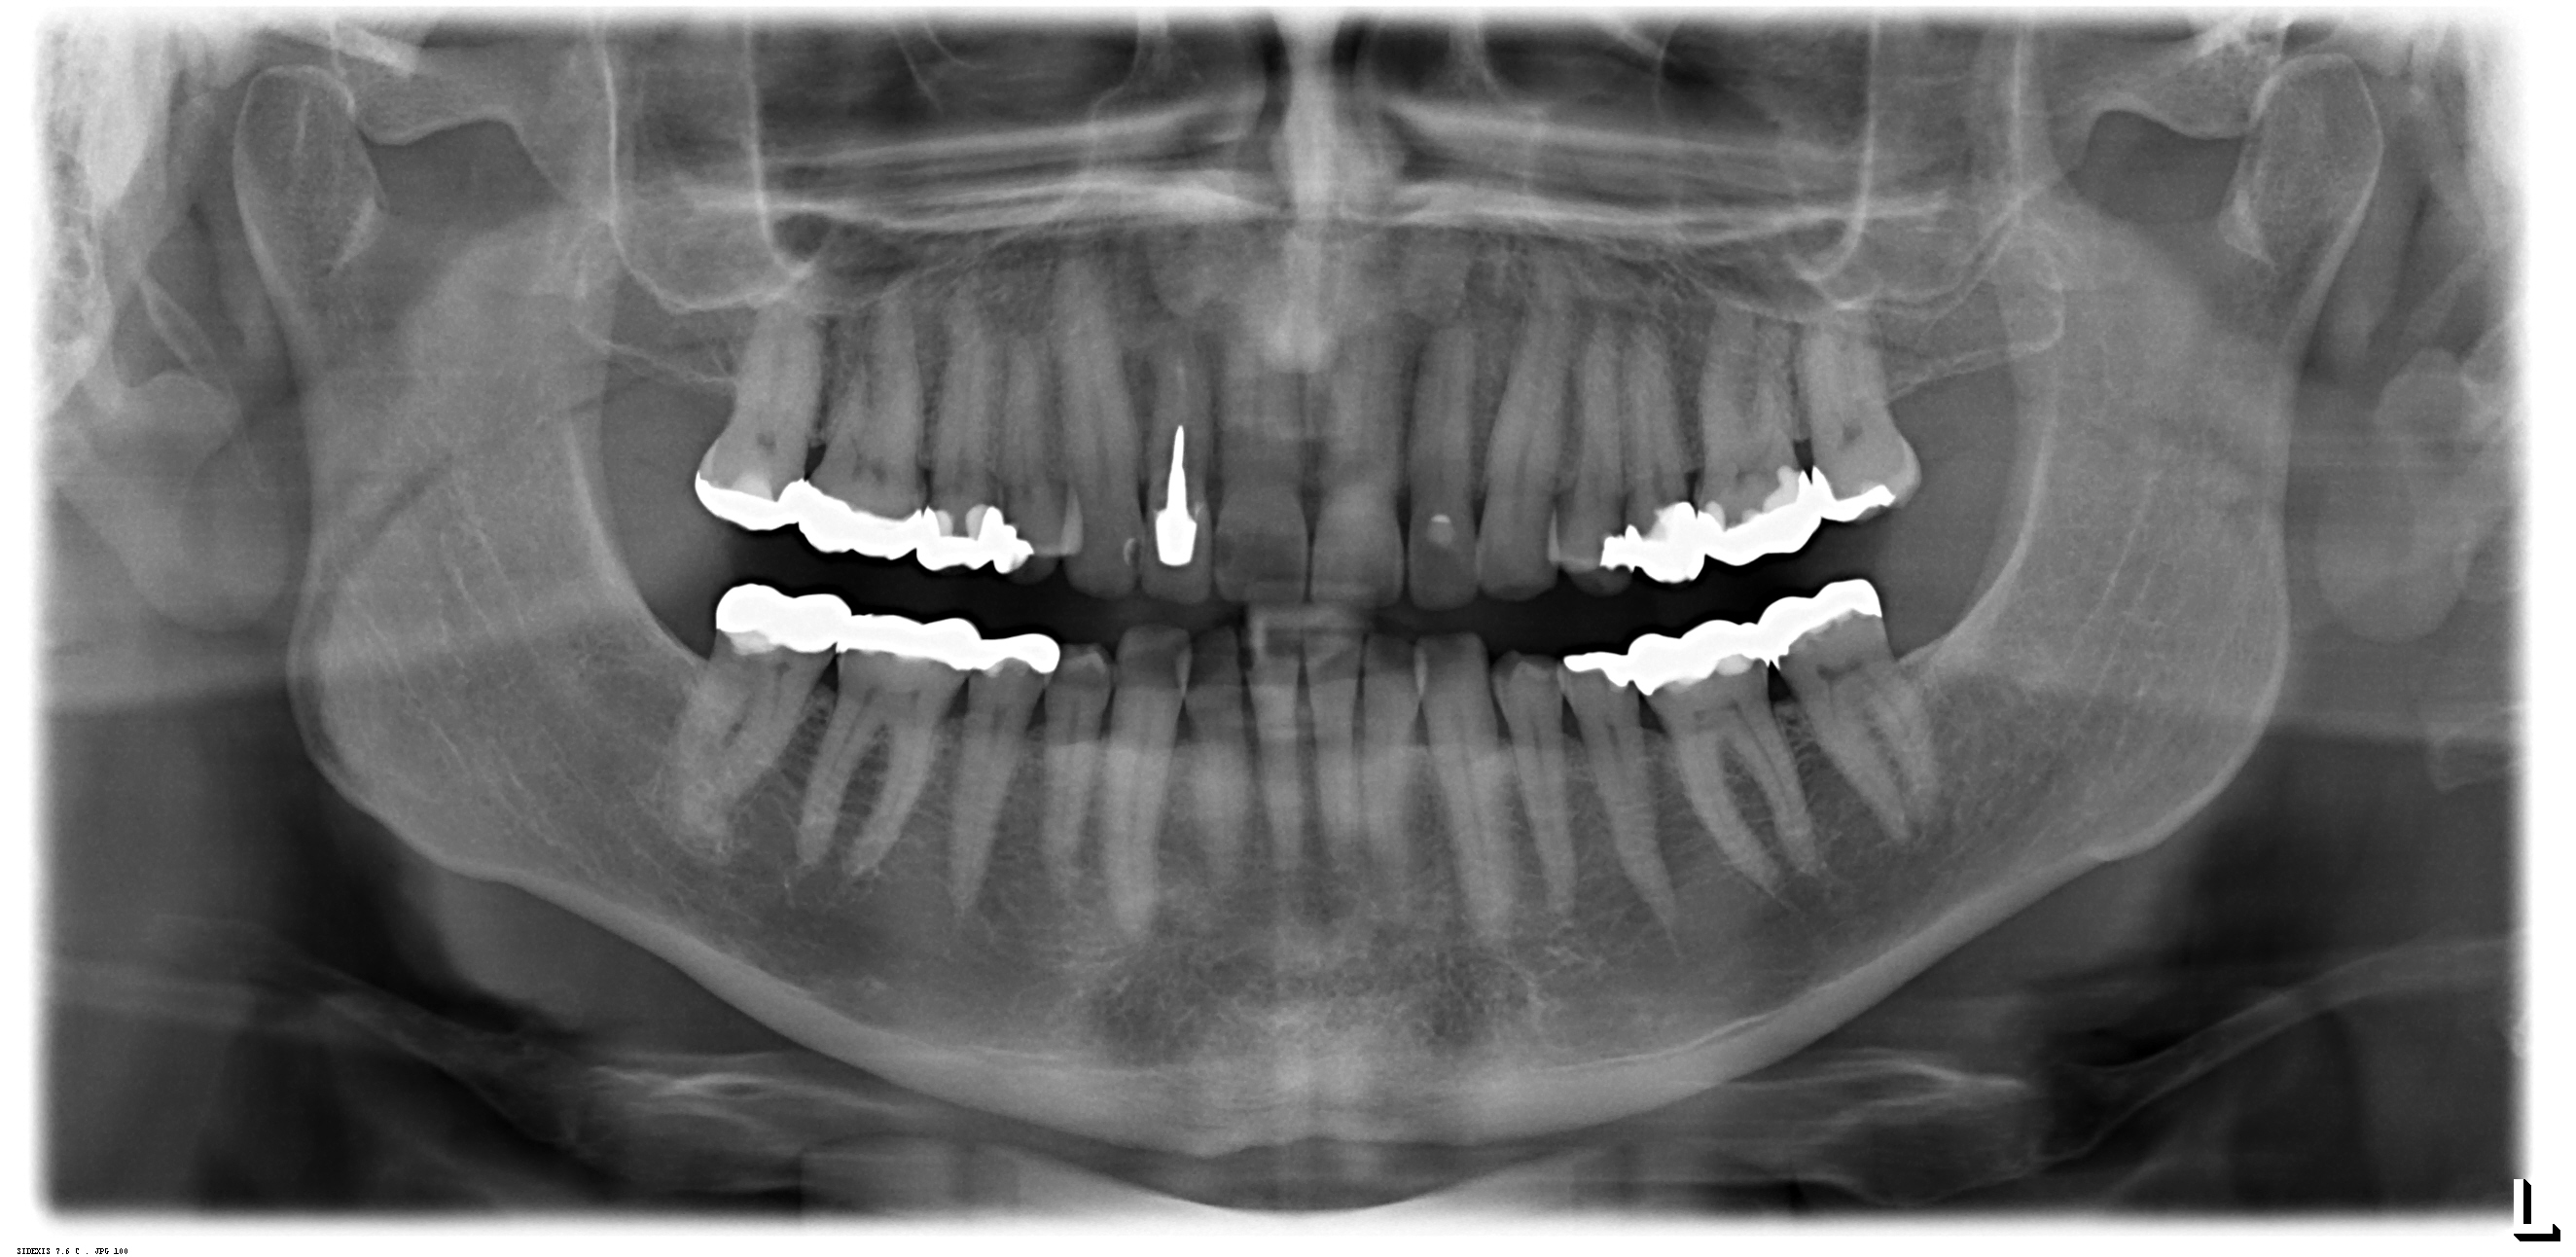

Digitales Röntgen

Röntgenaufnahmen als Einzelaufnahmen wie auch Übersichtsaufnahmen des ganzen Kiefers werden in unserer Praxis digital erstellt.

Die Strahlenbelastung gegenüber herkömmlichen Röntgenaufnahmen ist deutlich reduziert. Die Diagnostik verbessert.

Da keine Entwickler und Fixierbäder benötigt werden ist die Umwelt entlastet.